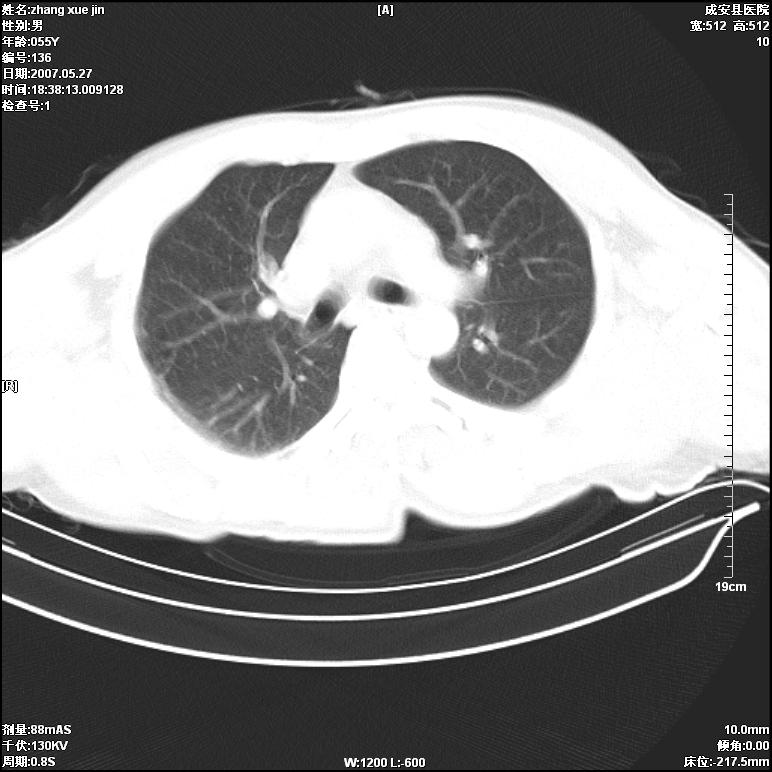

病人 男 53岁 从高处摔伤 行胸部ct检查,纵隔窗没事未上传,肺窗示,右侧胸膜下见条状稍高密度影,是胸膜下线还是右下肺轻度挫伤?意见不一,请分析。

右肺下叶胸膜下弧形窄带状模糊影,结合病史,考虑肺挫伤。

建议一周后复查,肺挫伤一般3~10天完全吸收。

支持肺挫伤,如果48小时阴影继续扩大,应疑有继发感染

倾向前者:正常肺坠积差

体位不正,左侧纵隔旁胸膜下亦见条带状略高密度影,考虑为坠积效应所致。

正常肺坠积差可能性大,

一定要明确的话得复查